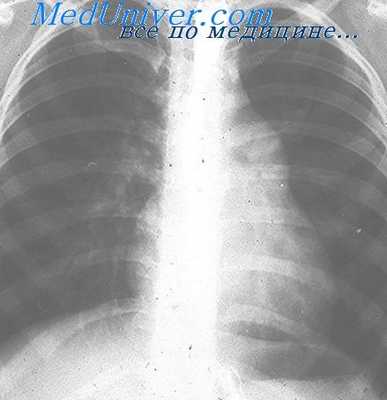

На ЭКГ при митральной регургитации могут наблюдаться признаки увеличения левого предсердия и гипертрофии левого желудочка, а также признаки мерцательной аритмии. При выполнении рентгенографии грудной клетки могут наблюдаться признаки застоя в малом круге кровообращения, увеличения левого предсердия и левого желудочка, а при развитии легочной гипертензии – правых отделов сердца.

Диагноз подтверждается данными рентгенологического и инструментальных методов исследования: фонокардиографией, электрокимографией, реовазографией и катетеризацией полостей сердца (Rudolf, Cayler, 1958; В. И. Бураковский, Б. А. Константинов, 1964; Ю. Д. Волынский с соавт., 1967, и др.).